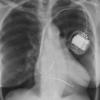

Pericardial stripe